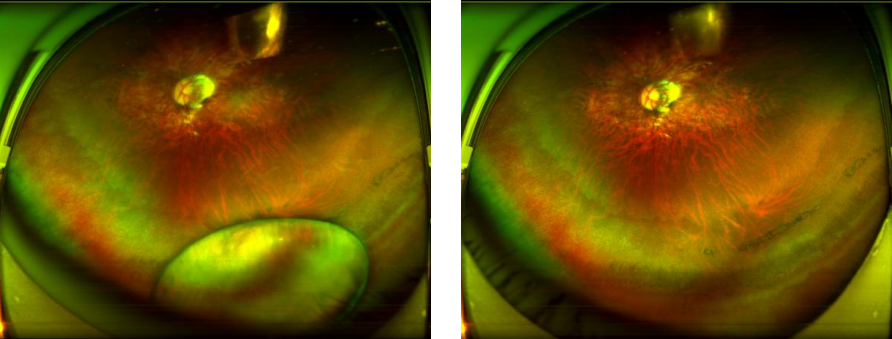

图:王先生术前(左)术后(右)眼底广角照相图

赵铁英院长经过详细的排查高度近视视网膜黄斑及周边情况后,交给朱远飞主任为其设计手术方案,并安全地实施了左眼玻璃体切除+脱位晶状体切除+眼内探查术;术后一个月对其右眼超高度近视并发性白内障,又进行白内障超声乳化摘除术+晶体张力环置入+人工晶体植入术。术后一个月复查,王先生双眼视力由术前0.05恢复到右眼 0.9,左眼 0.7的平衡状态,王先生摘掉了厚厚的眼镜,整个人年轻精神了很多,自言自语道:“我这还因祸得福了呢!以前戴着眼镜也没有这么清楚过!”不停对朱远飞主任、赵铁英院长及全体医护人员表达谢意。